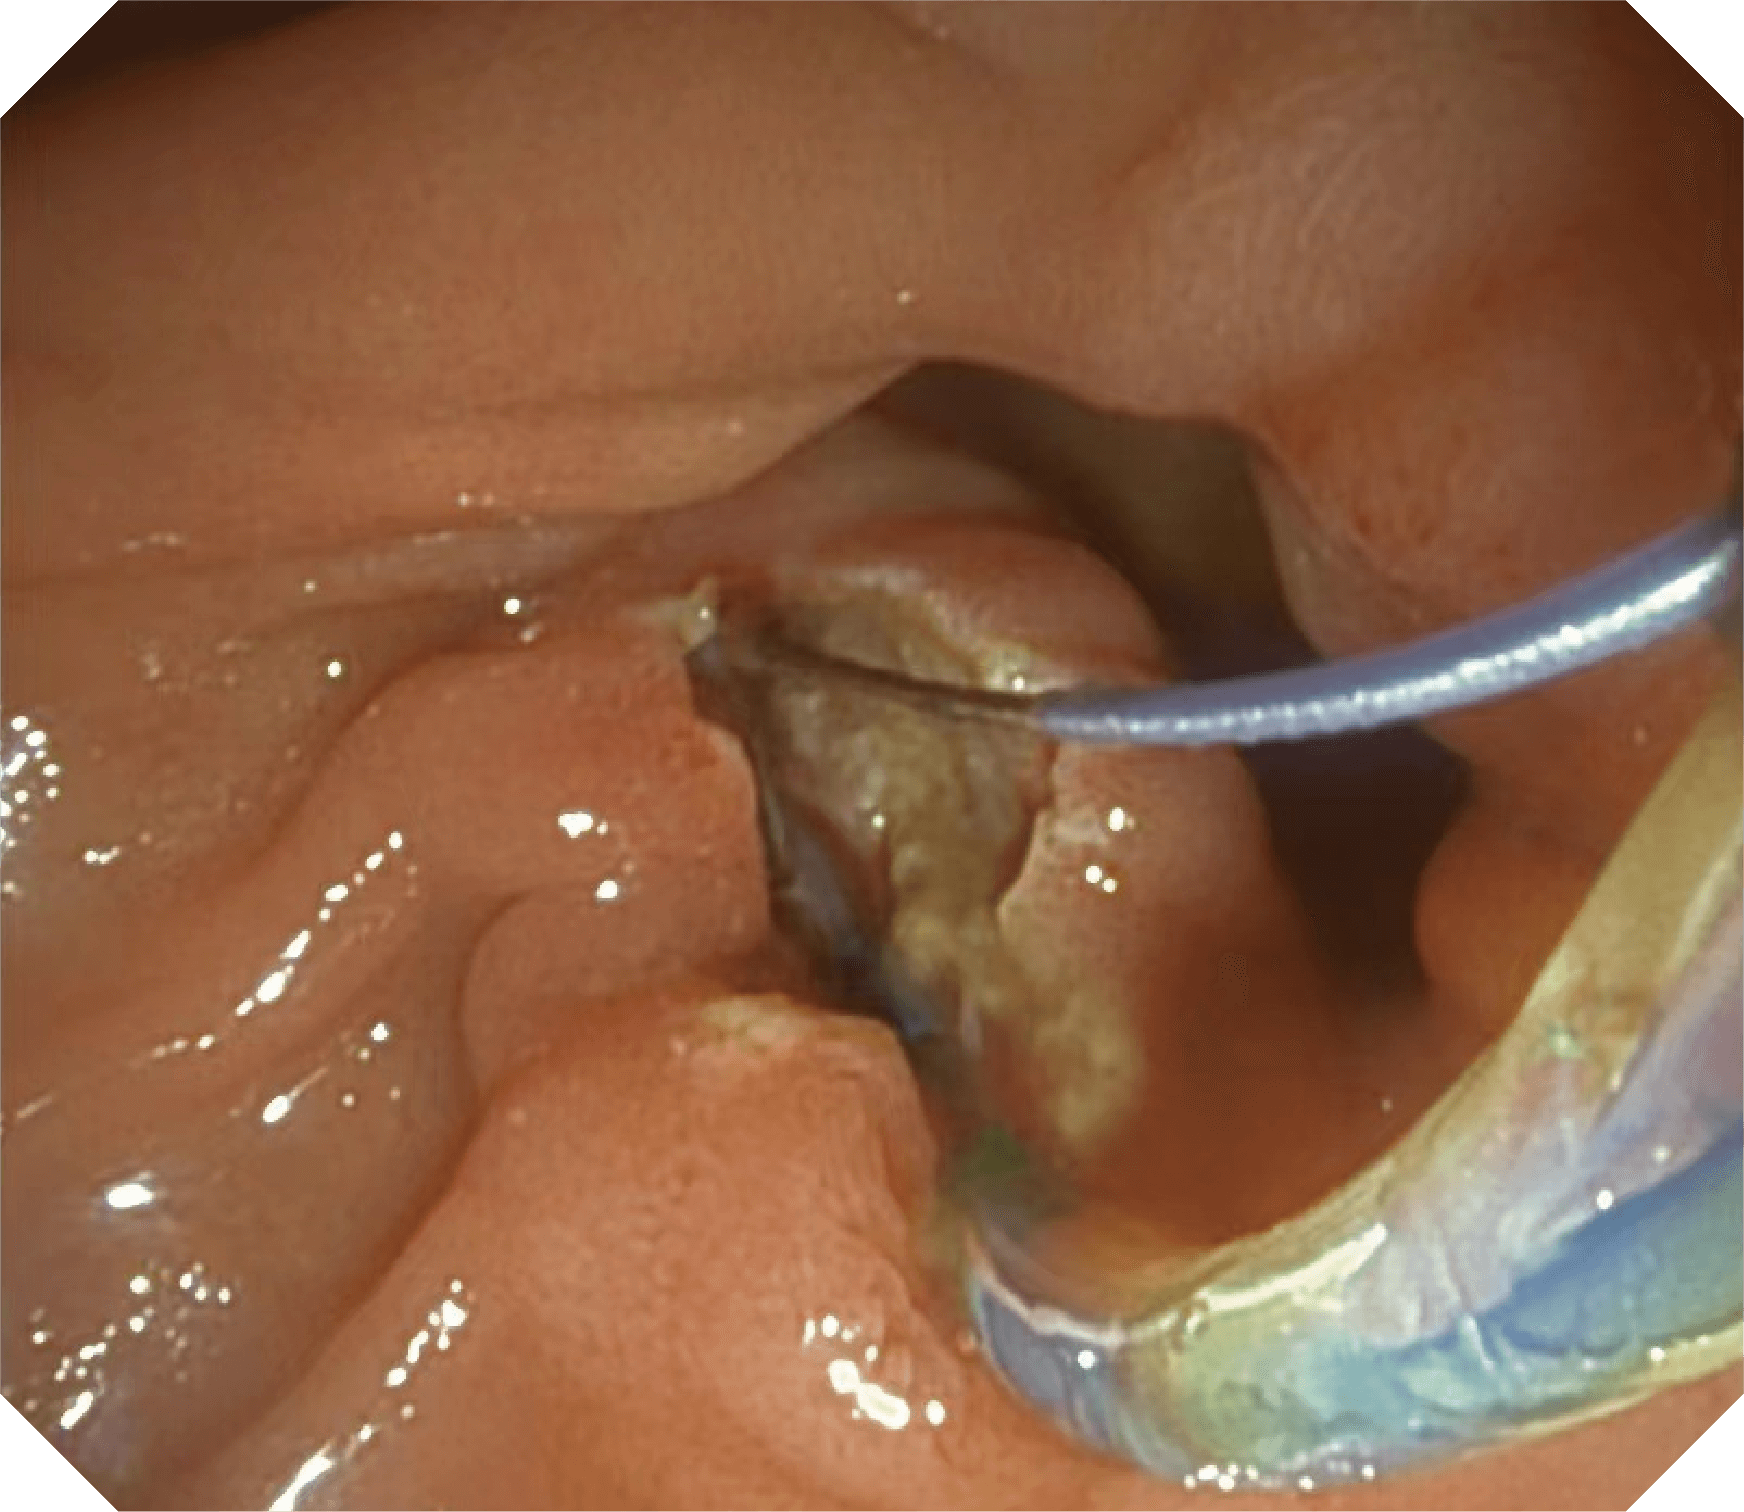

4.2mm大钳道,器械交换更顺畅

V槽设计提升导丝控制

更好的通过性,更稳定的镜体支撑力